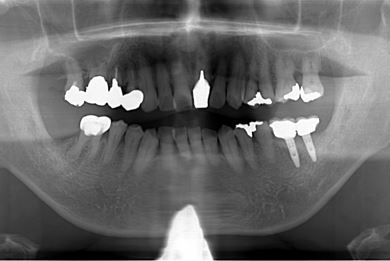

| 性別/年齢 | 男性 / 60歳 | ||||||||||||||||||||||||||||||||

| 主訴 | 右下奥歯の治療相談。(痛み・ぐらつき・物がかめない) | ||||||||||||||||||||||||||||||||

| 治療方針 | 左下奥の欠損部分をインプラント治療にて、機能的・審美的に回復を行う。 | ||||||||||||||||||||||||||||||||

| 治療内容 | インプラント2本、メタルボンドセラミッククラウン2本 | ||||||||||||||||||||||||||||||||

| 総治療費 | 680,610円 | ||||||||||||||||||||||||||||||||

| 治療期間 | 7ヶ月 |